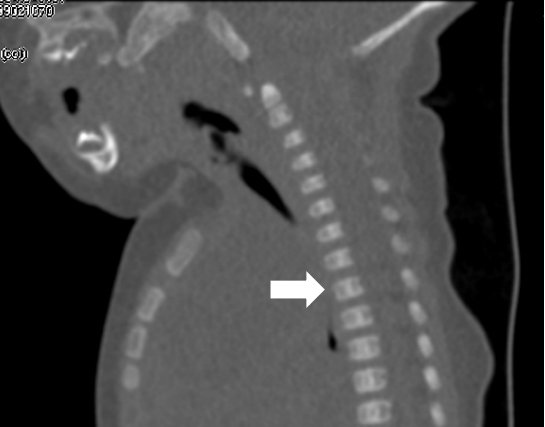

超声难以确诊的病例,或病变周围结构较复杂(如在颈部、纵隔等部位)以及位置较深(如在腹腔、盆腔等部位)治疗难度大、风险高时,往往需加做磁共振检查,更精确评估病情。当影像学检查难以诊断时,也可行诊断性穿刺,若穿刺抽出淡黄色清亮淋巴液即可诊断为淋巴管畸形,若抽出陈旧性血液结合细胞学检查可诊断为淋巴管瘤伴出血。

淋巴管囊肿磁共振检查

纵隔巨大淋巴管畸形压迫气管影响呼吸